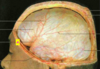

Label the types of extra-axial bleed occuring at the red; yellow & green arrows [3]

**red arrow: EDH** brown arrow shows how EDH respects the suture margins **yellow arrow points at SAH** **green arrow: SDH** blue arrow shows the fracture